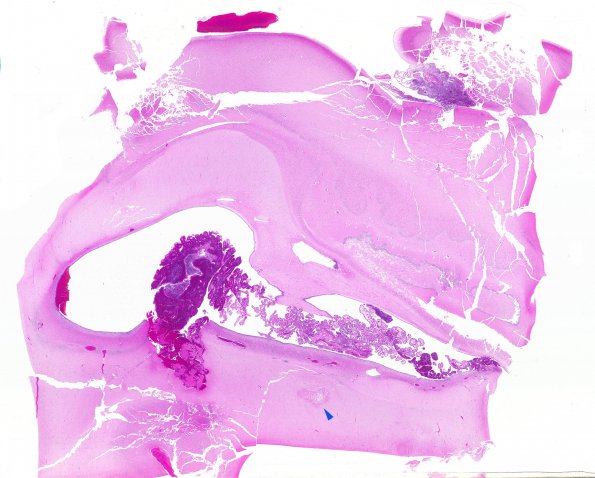

Washington University Experience | VASCULAR | Hemorrhage - Neonatal | 8A1 Hemorrhage, neonatal, choroid plexus (Case 8) H&E WM2 copy

8A1-4 In this case near term the source of the intraventicular hemorrhage is the choroid plexus. (H&E)